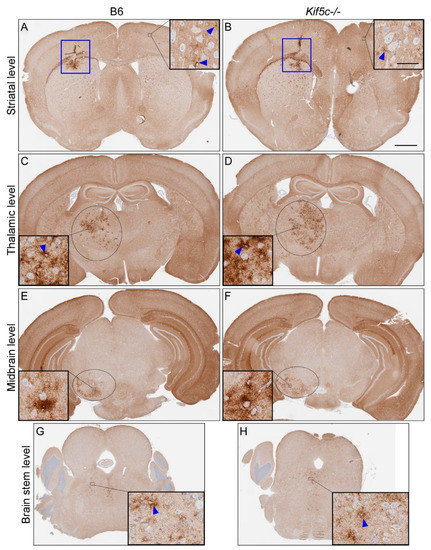

3.2. Stereotactic Kinetics of ME7 Scrapie at 40 Days Post-Inoculation (dpi)

| ME7 | B6 | 40 | Not tested | 4/4 | 1 | 0/4 | 0 | 0.17 | 2/4 | 0–1 | >0.99 | |

| Kif5c−/− | 40 | Not tested | 5/5 | 1 | 3/5 | 0–1 | 3/5 | 0–1 | ||||